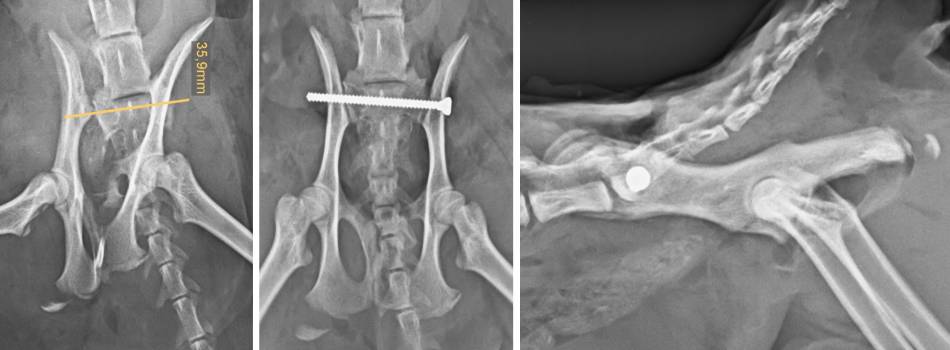

- einseitige Iliosakralluxation

- Bohrer: 2 mm

- Borhpunkg: Mitte des Halbmondes suchen und 1mm drüber und davor Borhrer Ansetzten

- Bohrrichtung: 20° nach caudal und 0° nach dorsal)

- bis mind. über 60% übers Ilium bohren

- Bohrung Ilium

- Zielgerät / Tuchklemme am Ilium in der Mitte des Halbmondes anklemmen um aussen eine Bohrmarkierung zu setzen

- 2,7 mm Bohrer durch Ilium bohren (etwas von caudal, damit es das Ilium nach aussen drückt

- Schraube setzen

- einseitige Luxation

- Zugschraube 2,7 mm

- Schraubenlänge mind. 60% vom Sakrum (ab 75% fällt die Komplikationsrate ab)